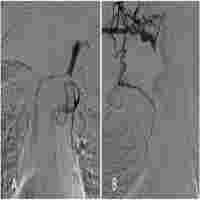

| Abstract | Introduction Superior vena cava (SVC) obstruction secondary to central venous catheterization is an increasingly recognized complication. Case presentation We present two cases of superior vena cava obstruction secondary to indwelling central venous catheters used for haemodialysis access. One of the patients developed the unusual complications of torrential epistaxis and haemoptysis, which has been reported only once so far in the literature. The other patient developed melaena secondary to downhill oesophageal varices. We briefly discuss the pathophysiology, symptoms and signs, investigations and management of superior vena cava obstruction and thrombosis. Conclusion Increasing use of central venous access for haemodialysis will increase the incidence of central venous stenosis, thrombosis and exhaustion. Superior vena cava obstruction is likely to be an increasingly recognised complication of vascular access in the future. |